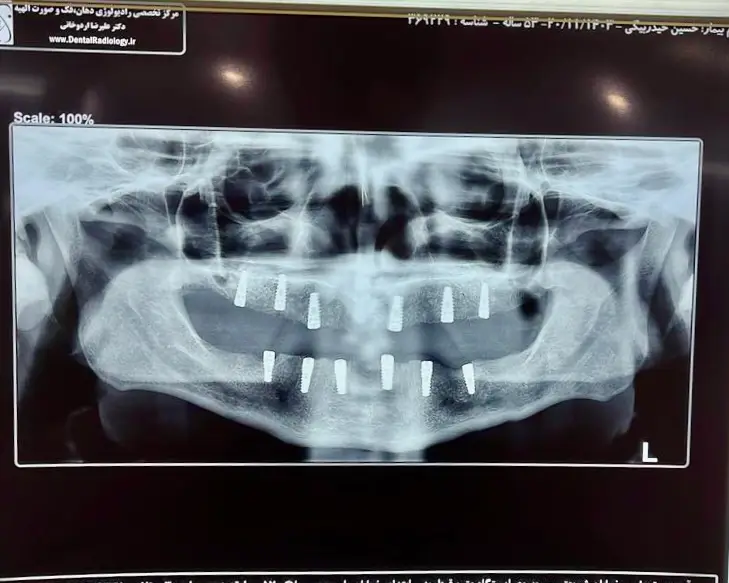

باز سازی کامل فک با ۱۲ واحد ایمپلنت naxis